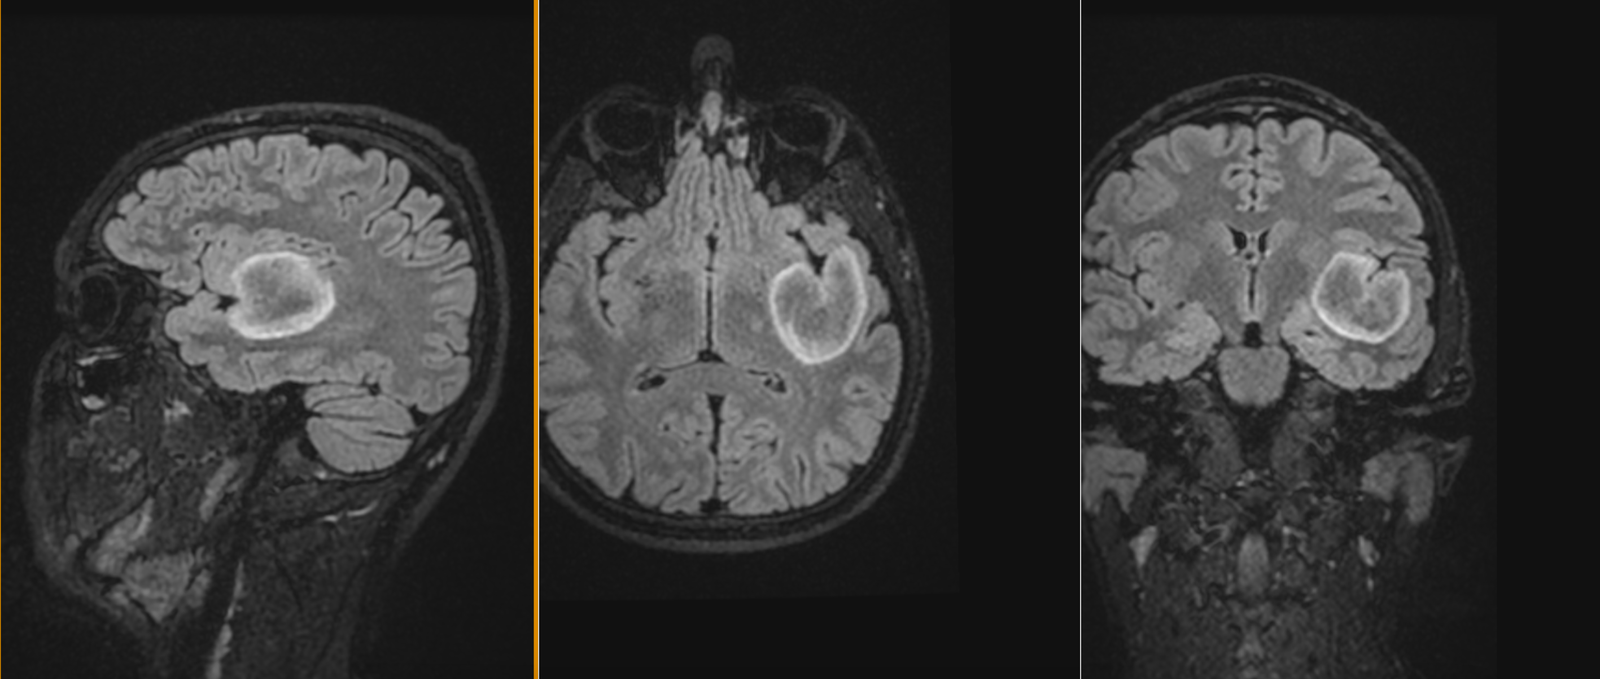

Tumora era bine delimitată, cu priză omogenă de contrast, și are origine din dura mater (foița externă a meningelui) de la nivelul șanțurilor olfactive – porțiunea din baza craniului pe unde trec nervii olfactivi. Aspectul RMN sugerează un diagnostic histopatologic de meningiom – tumoră benignă (în peste 95% din cazuri) .

Intervenția chirurgicală este cea mai bună soluție în asemenea situații, pentru că, deși benignă, tumora va continua să crească și va începe să determine și alte manifestări neurologice (crize comițiale, afectare vizuală, declin cognitiv – demență, etc.). De asemenea, cu cât tumor este mai mare, cu atât mai lungă și dificilă va fi operația, în timp ce pacientul va fi mai vârstnic și, posibil, cu mai multe suferințe cronice asociate. Un aspect care merită menționat este că portiunea posterioară a tumorii ajunge în apropierea celor doi nervi optici, fără a-i comprima (încă!).

RMN cerebral de control efectuat a doua zi după operație confirmă rezecția completă a tumorii și absența oricăror complicații.